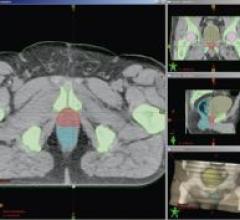

Varian Medical Systems’ new Smart Segmentation, a "smart" radiotherapy treatment planning tool, is designed to enable ...